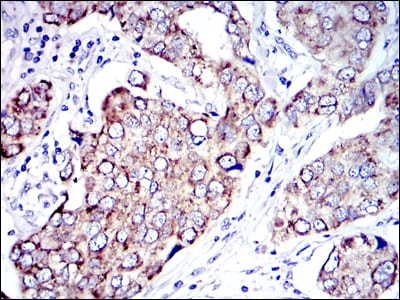

- Immunohistochemical analysis of paraffin-embedded human breast cancer tissues using AIF mouse mAb with DAB staining.